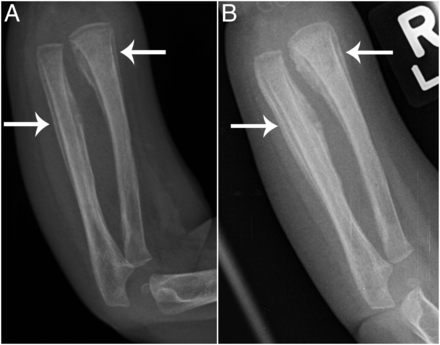

这种情况无须特殊处理,因为骨折原因不明,发病1周和2周后进行复查X线,提示骨折处鼓膜反应明显,骨膜炎加重,下图AB箭头所示。

图A是生病7天后的x线,图B是第二次就诊,也就是生病2周后的x线,图B提示鼓膜炎明显加重

复查的x线(上图B)提示骨膜炎加重,进行了右前臂的核磁检查,提示骨膜炎和肌炎。